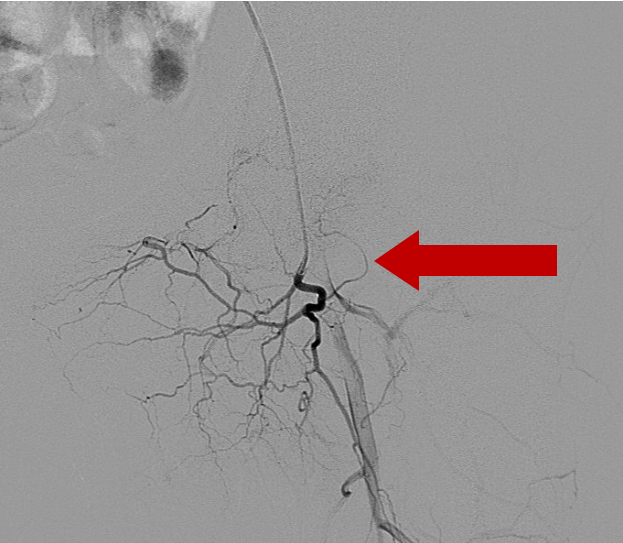

2020年8月7日介入手术,探查左股骨头供血动脉

介入手术中